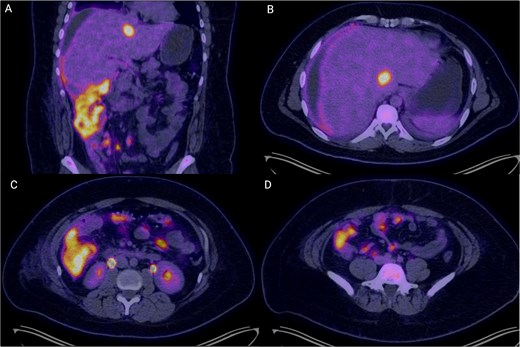

Colonoscopy demonstrated a right-sided subepithelial colonic lesion measuring ⁓30 mm (Fig. 1). Positron emission tomography-computed tomography (PET-CT) revealed circumferential thickening of the ascending colon with intense fluorodeoxyglucose (FDG) uptake (SUVmax 20.0), along with multiple peritoneal implants, mesenteric, perigastric, and right subdiaphragmatic lymphadenopathy, as well as hypermetabolism in the previously identified hepatic lesion (SUVmax 19.8), findings highly suggestive of neoplastic dissemination (Fig. 2).

PET-CT images demonstrating extensive hypermetabolic abdominal disease. (A) Coronal image showing circumferential mural thickening of the right colon with intense FDG uptake (SUVmax 20.0), suggestive of transmural neoplastic infiltration, alongside multiple peritoneal implants and mesenteric hypermetabolism. (B) Axial slice at the hepatic level revealing a hypodense, hypermetabolic lesion in segment VI of the liver (SUVmax 19.8), consistent with a secondary metastatic deposit. (C) Axial mid-abdominal view showing abnormal FDG uptake in mesenteric and pericolonic regions, with nodular foci consistent with lymphadenopathy and peritoneal seeding. (D) The inferior axial section depicts multiple hypermetabolic foci along the peritoneum, indicative of diffuse peritoneal involvement. These findings are consistent with metabolically active, disseminated abdominal disease in keeping with a diagnosis of high-grade lymphoma.